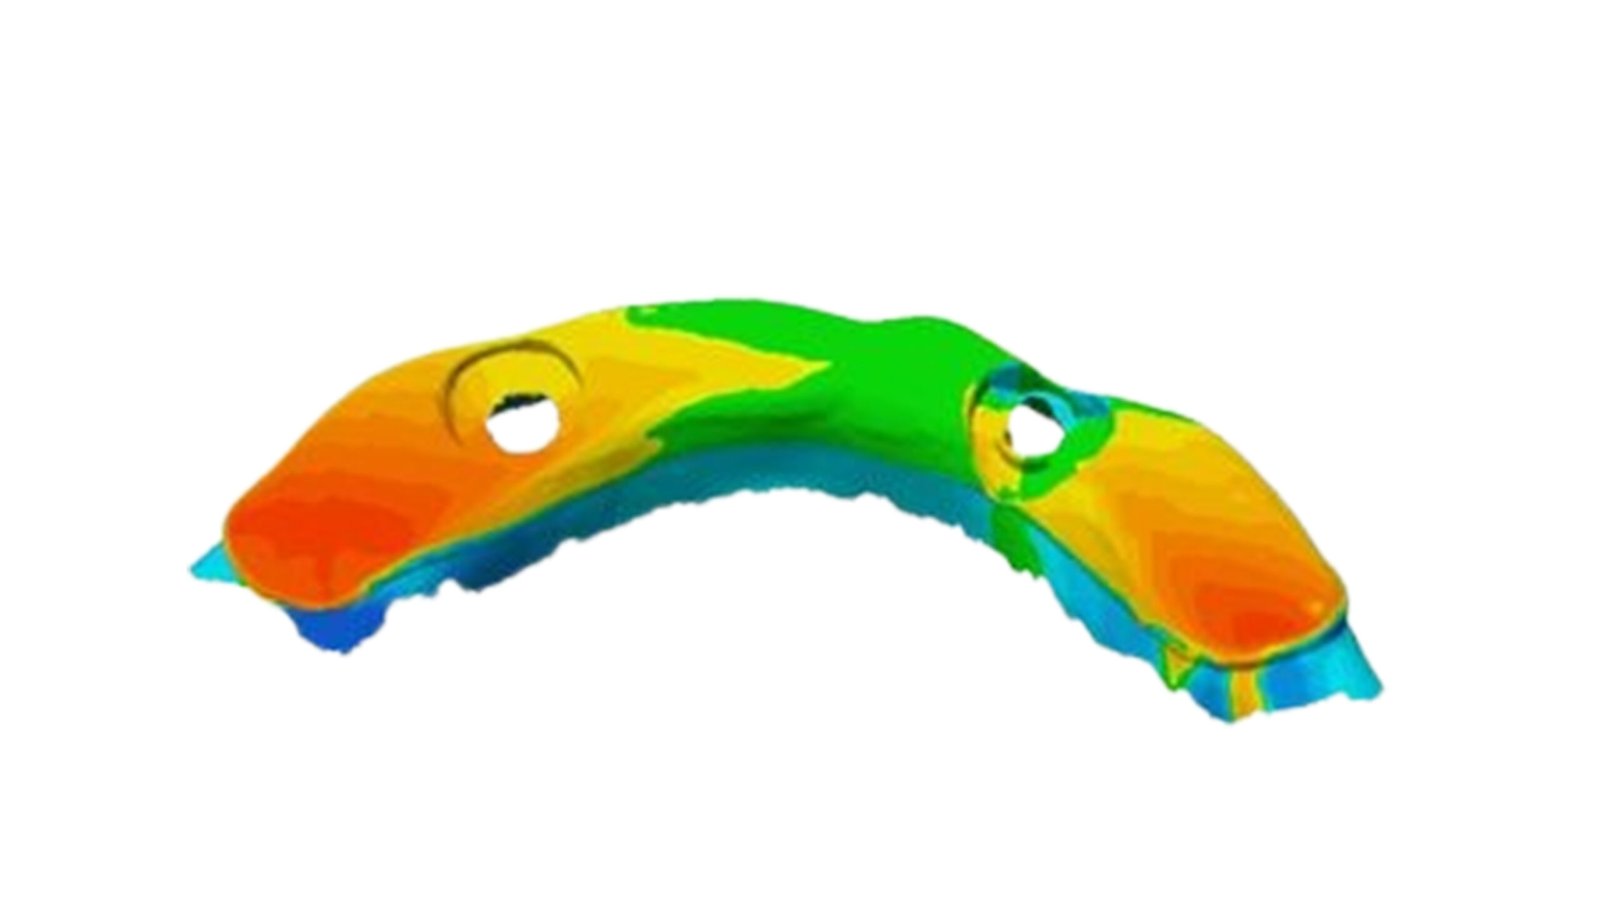

This section specializes in high-precision 3D deviation mapping to compare pre- and post-treatment anatomical or implant-related geometries. Using advanced superimposition and deviation algorithms, we quantify micro-level shifts, deformation zones, and structural discrepancies with sub-millimeter accuracy. These analyses support quality control, surgical verification, and design validation. The resulting deviation heat-maps provide clear, data-driven insights that enhance clinical decision-making and device optimization.